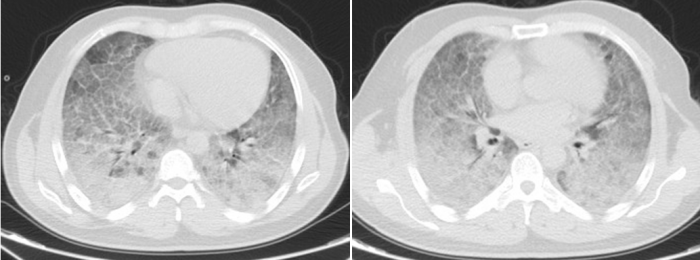

李贤胸部CT显示其双肺已呈现“大白肺”状态

历经31天鏖战,李贤的肺部影像从“白茫茫一片”逐渐恢复透亮,鼻导管吸氧下血氧饱和度稳定在90%以上,最终好转出院。患者家属含泪致谢:“是91短视频